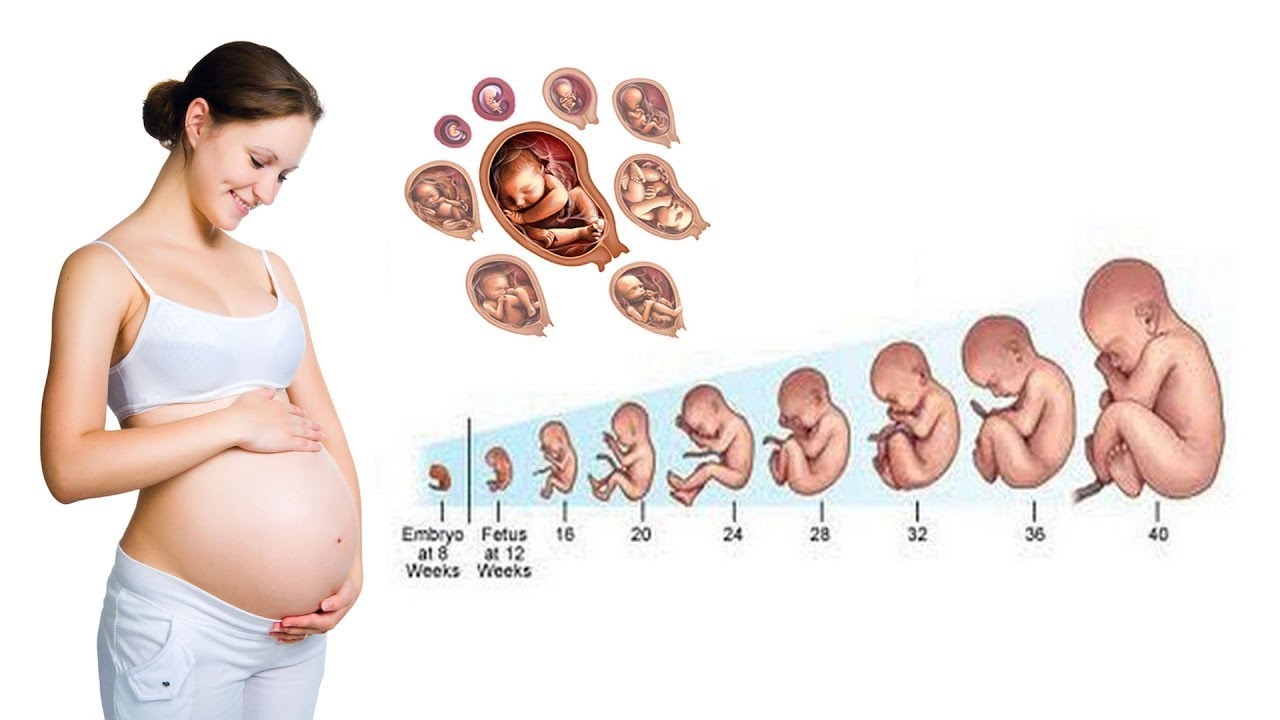

Фотография Плода В Животе

Фотография Плода В Животе 113 фотографий